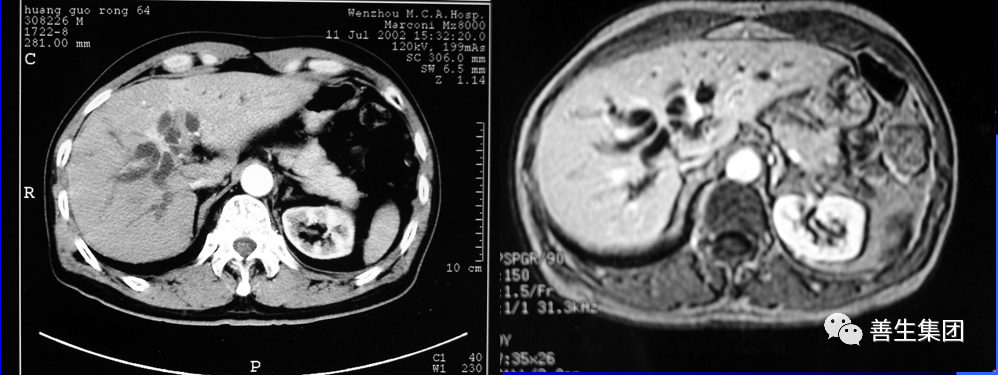

皮肤巩膜黄染伴皮肤瘙痒20余日,胰头MT。

胆管支架什么样子经皮肝胆管穿刺置管引流术(PTCD)及胆道内支架临床应用_https://www.jmylbn.com_新闻资讯_第14张

MIR和CT

胆管支架什么样子经皮肝胆管穿刺置管引流术(PTCD)及胆道内支架临床应用_https://www.jmylbn.com_新闻资讯_第15张

PTC造影+MIR胆道

胆管支架什么样子经皮肝胆管穿刺置管引流术(PTCD)及胆道内支架临床应用_https://www.jmylbn.com_新闻资讯_第16张

双导丝+左右肝管分别引流